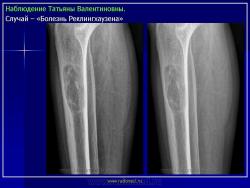

ГИПЕРПАРАТИРЕОИДНАЯ ОСТЕОДИСТРОФИЯ (ПАРАТИРЕОИДНАЯ ОСТЕОДИСТРОФИЯ «БОЛЕЗНЬ РЕКЛИНГХАУЗЕНА»).

Пораженные длинные трубчатые кости несколько вздуты. Это цилиндрическое утолщение захватывает весь диафиз, метафизы также представляются несколько вздутыми. Кортикальный слой неравномерно истончается, может быть бугристым. Эпифизы, как правило, мало изменены. Характерна деформация метадиафиза бедренной кости по типу «пастушьей палки». Область большого вертела поднимается, анатомическая шейка бедренной кости располагается горизонтально, диафиз О-образно искривляется. Характерна также варусная деформация проксимального отдела плечевой кости. Деформации обычно не симметричны. Достаточно быстро развивается деформация костей таза в виде «карточного сердца». Реакция надкостницы отсутствует и лишь при патологических переломах, может выявляться незначительная периостальная реакция.

На рентгенограммах определяется перестройка костной структуры в виде очагового или диффузного крупнозернистого остеопороза. Характерна кистозная перестройка костной структуры. Кисты располагаются, как в зоне костномозгового канала, так и интракортикально. Форма их - овальная, вытянутая по длиннику кости. Кисты могут быть одиночными и множественными. Часто кисты сливаются одна с другой и в зоне костномозгового канала они имеют нечеткие контуры.